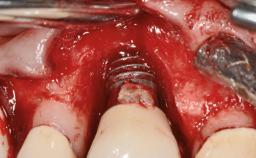

A 77-year-old male patient was referred for the management of frequent and repeated acrylic fracture of his existing mandibular fixed full-arch implant-supported metal/acrylic prosthesis. He also complained about softtissue soreness and the lack of retention and stability of his maxillary removable partial metal/acrylic prosthesis. Both prostheses had been delivered two years previously as part of his full-mouth rehabilitation (caries, tooth wear, tooth fracture). His medical history revealed high blood pressure, controlled with the use of antihypertensive medication.

# of Implants | 5 |